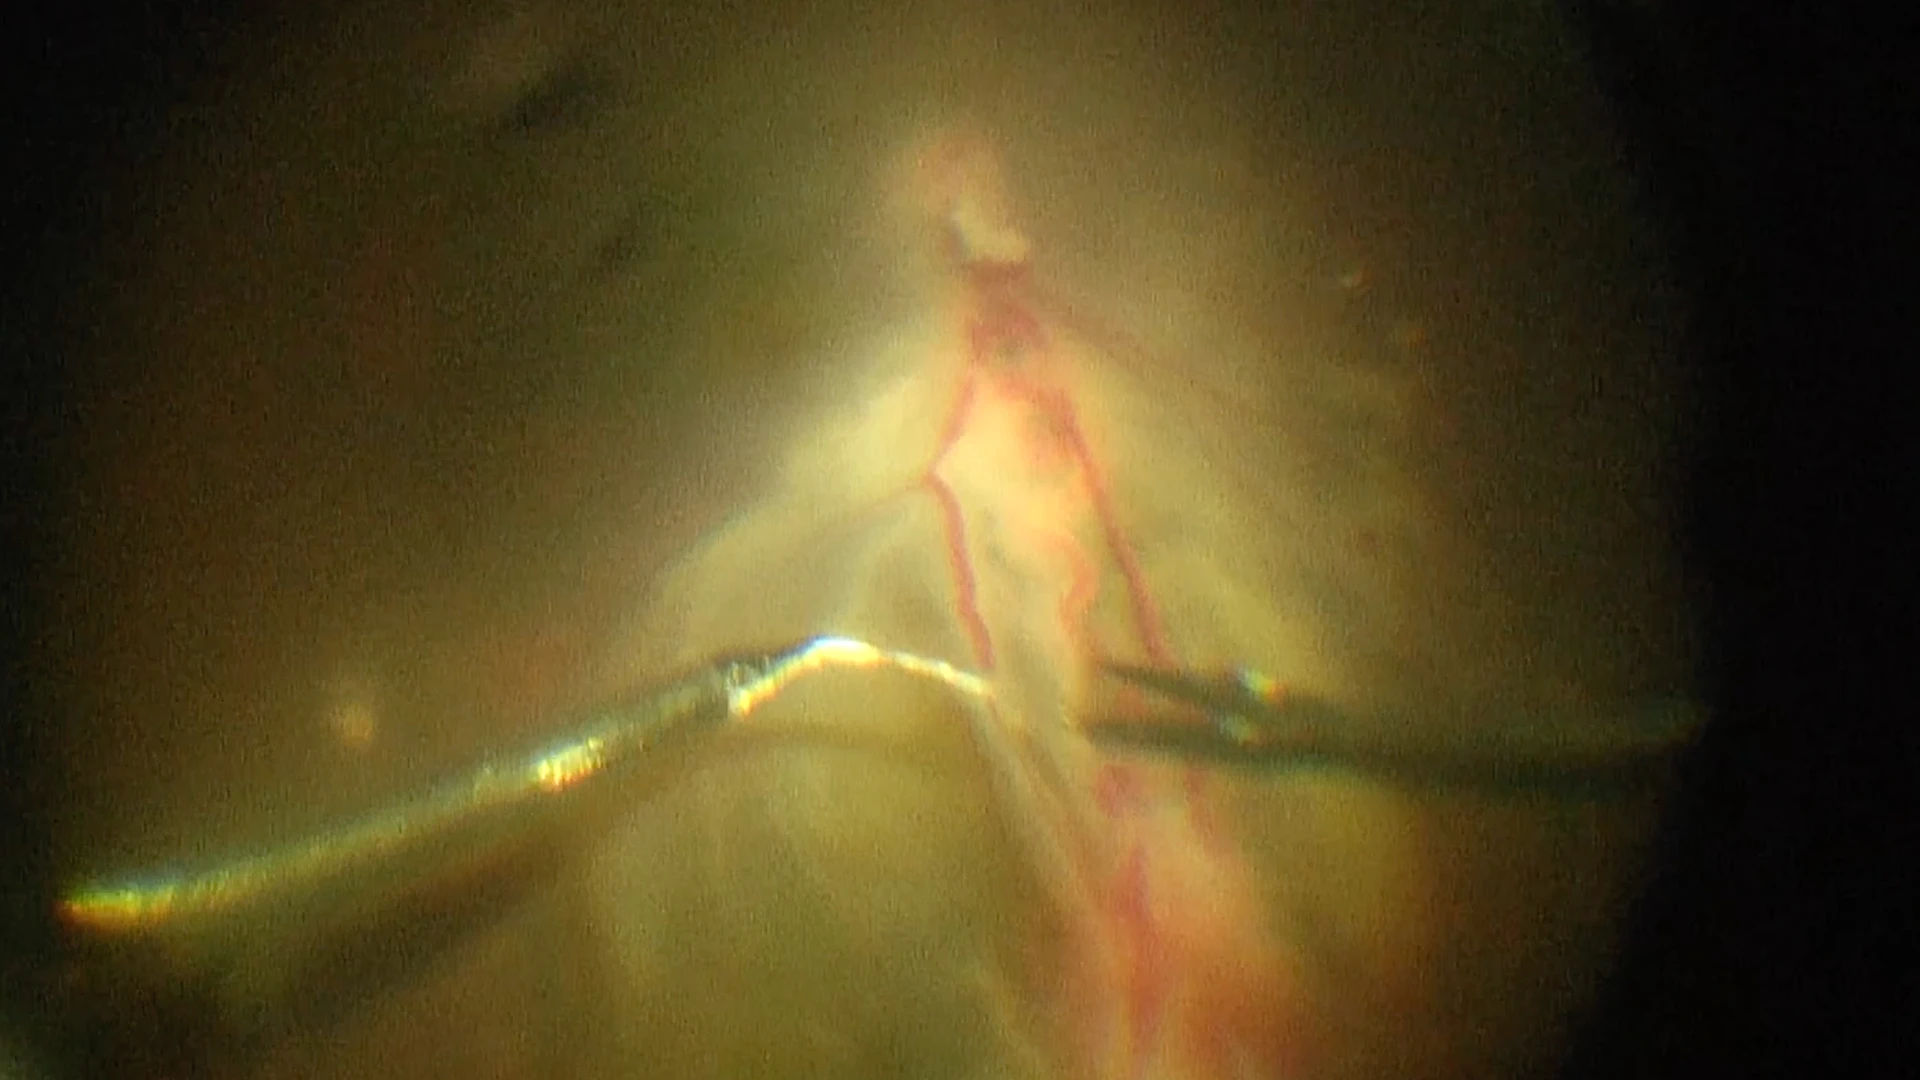

Surgical diagram showing key steps performed by Dr. Landa and Dr. Patel, including tumor removal, vessel ligation, and laser therapy to repair the retinal detachment (Gregory © 2025 Mount Sinai Health System)

Ligation of the two abnormal vessels using intraocular forceps and sutures